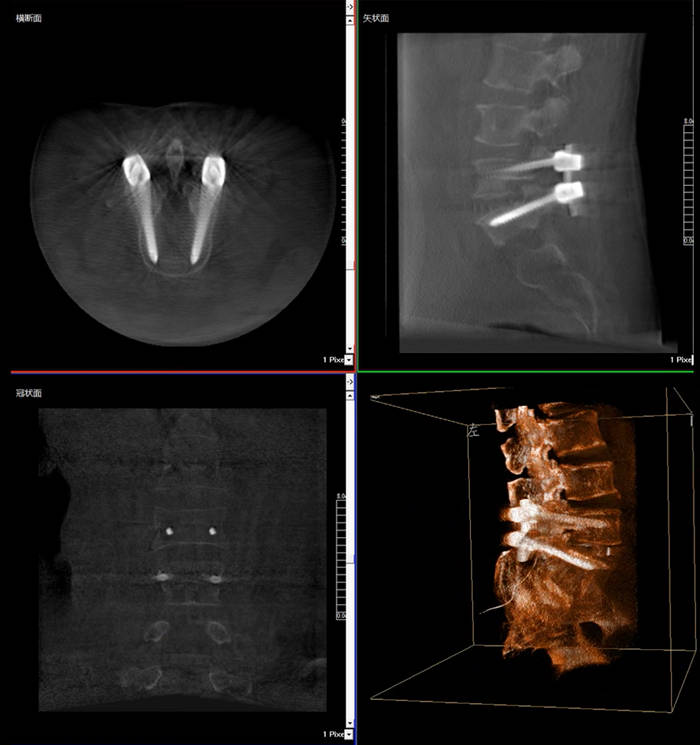

普愛醫(yī)療三維C臂X光機快速生成橫斷面、矢狀面、冠狀面斷層圖像和三維立體圖像,方便醫(yī)生確認(rèn)手術(shù)部位。三維C臂X光機的大平板帶來出色的顯示視野,可以更好的顯示手術(shù)部位全局情況,確保手術(shù)規(guī)劃及執(zhí)行的準(zhǔn)確性。

三維C臂X光機影像

普愛醫(yī)療三維C臂X光機二維、三維成像模式可快速切換,僅需30秒鐘,一鍵從二維切換至“術(shù)中CT”模式,完成術(shù)中三維圖像采集,同步生成“類CT”斷層圖像,方便醫(yī)生從各個角度各個層面來觀察病灶區(qū)域,準(zhǔn)確定位穿刺針位置。采用30CM*30CM的動態(tài)平板探測器,成像范圍大(一次性可成像5節(jié)腰椎),無需反復(fù)透視,節(jié)約手術(shù)時間。